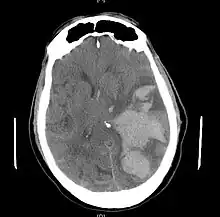

| MRI showing injury due to brain herniation | |

Brain herniation is a potentially deadly side effect of very high pressure within the skull that occurs when a part of the brain is squeezed across structures within the skull. The brain can shift across such structures as the falx cerebri, the tentorium cerebelli, and even through the foramen magnum (the hole in the base of the skull through which the spinal cord connects with the brain). Herniation can be caused by a number of factors that cause a mass effect and increase intracranial pressure (ICP): these include traumatic brain injury, intracranial hemorrhage, or brain tumor.[1]

Treatment involves removal of the etiologic mass and decompressive craniectomy. Brain herniation can cause severe disability or death. In fact, when herniation is visible on a CT scan, the prognosis for a meaningful recovery of neurological function is poor.[2] The patient may become paralyzed on the same side as the lesion causing the pressure, or damage to parts of the brain caused by herniation may cause paralysis on the side opposite the lesion.[11] Damage to the midbrain, which contains the reticular activating network which regulates consciousness, will result in coma.[11] Damage to the cardio-respiratory centers in the medulla oblongata will cause respiratory arrest and (secondarily) cardiac arrest.[11] Investigation is underway regarding the use of neuroprotective agents during the prolonged post-traumatic period of brain hypersensitivity associated with the syndrome.[17]